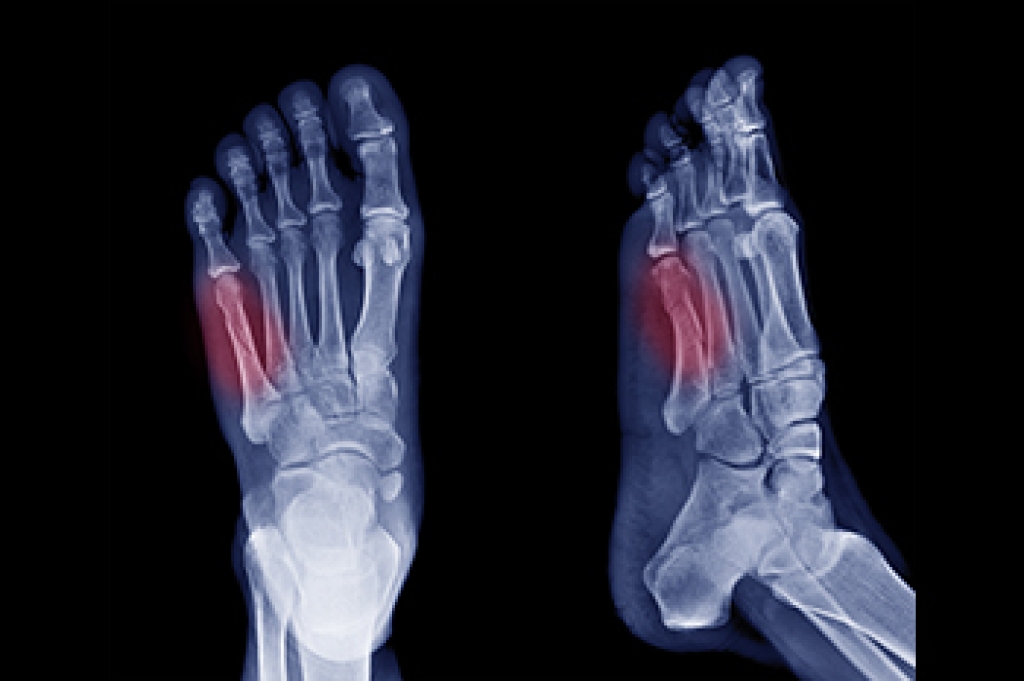

A dancer's fracture is a break in the shaft of the 5th metatarsal, the long bone on the outer side of the foot. This injury is typically caused by twisting motions, awkward landings, or direct trauma. It is common among dancers and athletes but can happen to anyone. Symptoms of a 5th metatarsal fracture include sharp pain on the outer side of the foot, swelling, bruising, tenderness, and difficulty walking. Diagnosis is made through a physical examination and imaging, such as X-rays, to determine the exact location and severity of the fracture. Treatment often involves immobilizing the foot with a cast or walking boot to allow the bone to heal properly. In severe cases, surgery may be required to realign and stabilize the bone. A podiatrist can provide expert care and ongoing monitoring to ensure the foot heals correctly and regains full functionality. If you have fractured your foot, it is suggested that you schedule an appointment with a podiatrist for a diagnosis and treatment options.

A broken foot is caused by one of the bones in the foot typically breaking when bended, crushed, or stretched beyond its natural capabilities. Usually the location of the fracture indicates how the break occurred, whether it was through an object, fall, or any other type of injury.

Those that suspect they have a broken foot shoot seek urgent medical attention where a medical professional could diagnose the severity.

Treatment for broken bones varies depending on the cause, severity and location. Some will require the use of splints, casts or crutches while others could even involve surgery to repair the broken bones. Personal care includes the use of ice and keeping the foot stabilized and elevated.